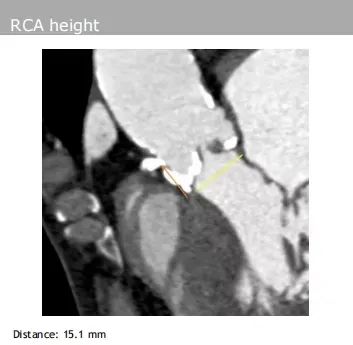

左、右冠脉高度:分别为17.2 mm、15.1 mm,且双侧冠脉开口均有钙化